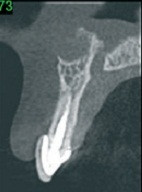

女,十岁,单侧唇腭裂致21牙、22、12牙畸形,且21牙、22牙间牙槽骨发育不全。经自体髂嵴骨移植后,拔除21牙、22牙行正畸治疗以将23牙移动至22牙位置。同时将正畸需拔除的下颌第一前磨牙移植到21牙的牙槽窝内。并在正畸治疗结束后树脂恢复21牙、22牙形态。患者18岁时拔除左上颌乳尖牙行种植义齿修复。